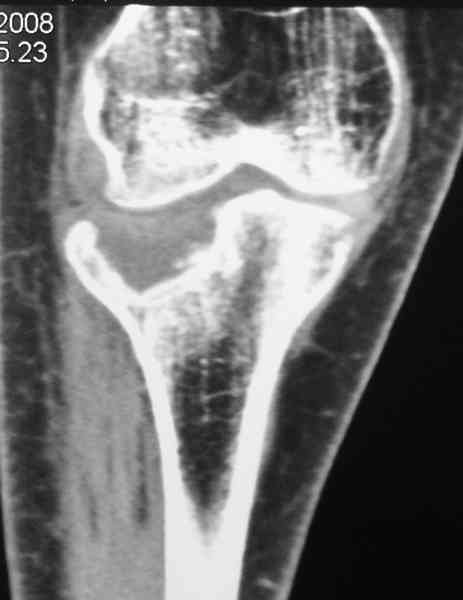

Застарелый перелом 41С3

Обратился больной 46л. 3-месяца назад в каком-то городке Дальнего Востока упал с высоты, сделана Р-графия, наложена гипсовая повязка, от предложенной операции отказался и уехал домой, дальше где и как лечился, не говорит.

Ходит при помощи двух костылей, жалобы на боли при нагрузке, в покое и при движении, без нагрузке боли нет, разгибание 175 гр, сгибание 90 гр, симптомов повреждения связочного аппарата к/с не определяется, от предложенного артродеза пока отказывается.

По тактике лечения, более импонирует второй вариант, но наружная плато расколота и туда при нагрузке внедряется н/мышелка бедра, поэтому после дистракции как репонирвать: или стяжными винтами, или изогнутами спицами или субхондральная костная пластика?

У пациента основной проблемой является импрессионый перелом наружного мыщелка, уже неправильно сросшийся, по-видимому. Аппаратом закрыто можно только подправить угол на уровне метадиафиза. Что

улучшит разве что внешний вид конечности, но не решит основной проблемы - грубой деформации суставной поверхности.